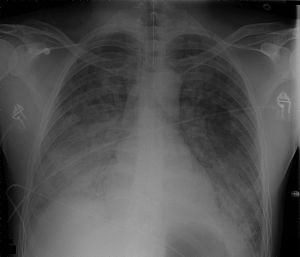

Chest Xray 40 yr old male acute respiratory distress syndrome as a complication of murine typhus. 13-1421-F1.jpg

Chest Xray of a 40 yr old male in acute respiratory distress syndrome as a complication of murine typhus